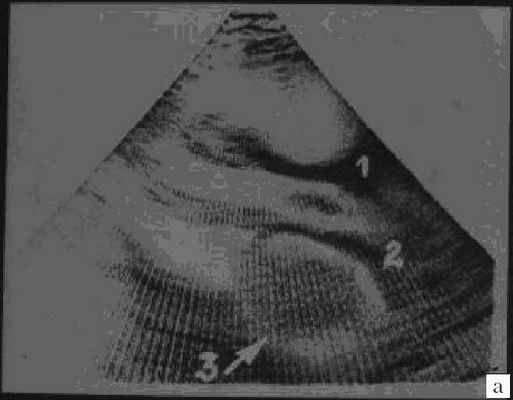

Рабдомиомы - самые частые опухоли сердца у детей. В 50-80% случаев они сочетаются с туберозным склерозом. Гистологически представлены крупными веретеновидными вакуолизированными клетками с большими запасами гликогена, сдвинутым на периферию ядром и гранулярной цитоплазмой. Макроскопически рабдомиомы нередко множественные, серо-желтого цвета, размером от мелкой горошины до гигантского относительно сердца узла, поражают стенки камер сердца и перегородки, могут распространяться как в полость желудочка (рис. 1), так и экстракардиально (рис. 2).

Рис. 1. Опухоль сердца (обозначена маркерами), исходящая из межжелудочковой перегородки в полость левого желудочка.

Рис. 2. Опухоль левого желудочка, распространяющаяся в основном экстракардиально и исходящая из стенки левого желудочка с переходом на межжелудочковую перегородку.

Миксомы построены из перегруженных липидами многоядерных клеток, погруженных в миксоидную строму, богатую гликозаминогликанами. Клетки располагаются группами вокруг сосудов. В 10% случаев в опухоли обнаруживаются депозиты кальция. Миксомы свойственны подросткам (рис. 3), у детей встречаются редко. Более 80% всех миксом исходят из межпредсердной перегородки и митрального клапана. Миксома может быть как спорадической (90% случаев), так и семейной опухолью (10%), наследуемой аутосомно-доминантно (миксомный синдром) в рамках синдрома Карнея [3, 4]. При семейном варианте миксома обычно множественная и склонна к рецидивированию [5, 6].

Рис. 3. Миксома левого предсердия.

а) 1 и 2 - стенка аорты, 3 - миксома.

б) Макропрепарат удаленной миксомы.